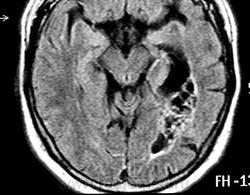

ГМ. Субэпендимома 2. +

Субэпендимома